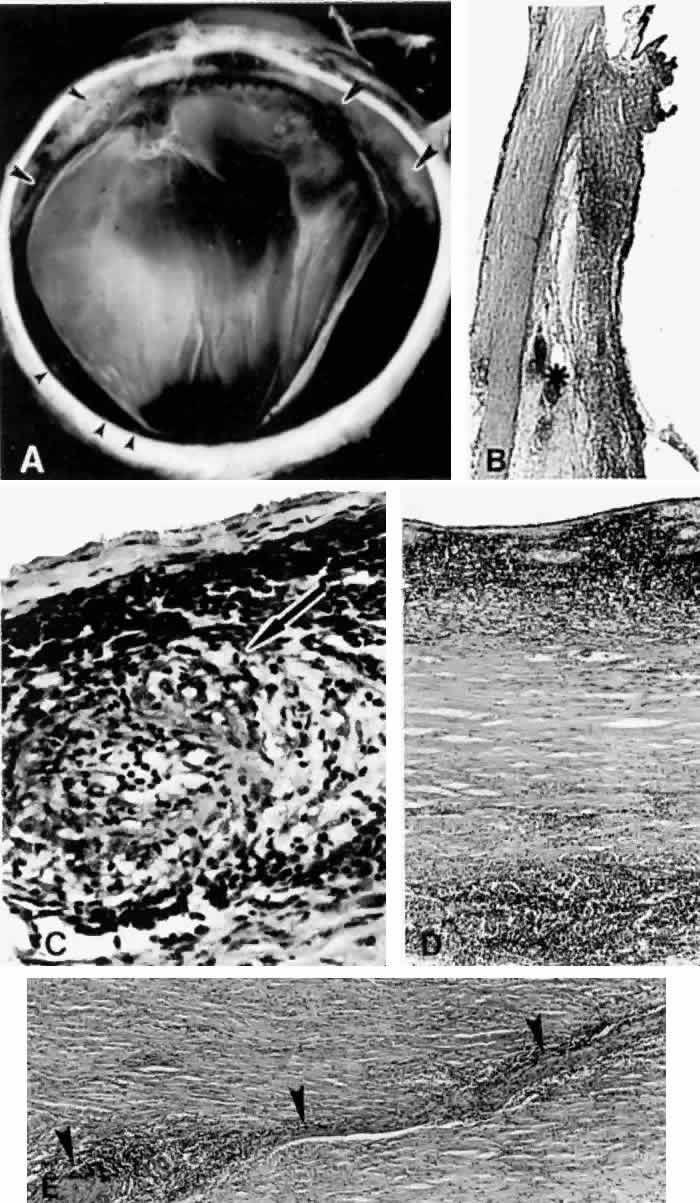

Fig. 8. This choroidal and ciliary body detachment, which occurred after intracapsular cataract extraction, was mistaken for a malignant melanoma.39 A. Iris incarceration in the wound (arrow) and extensive ciliary body effusion consisting of a dense, proteinaceous material (asterisk) (H & E, × 115). B. Effusion of the choroid near the ora serrata by a moderately dense, proteinaceous material without inflammatory cells. Note folds of choroid (arrowheads) (H & E, × 115).

Fig. 9. A. This serosanguineous ciliochoroidal effusion (arrow), which occurred after iridectomy for an iris melanoma in a 68-year-old man, was mistaken for a choroidal melanoma (H & E, × 25). B. Site of the limbal wound (arrowhead) with incarceration of the iris base and residual melanoma in the iris, anterior aspect of the ciliary body, and trabecular meshwork (H & E, × 60).

Fig. 10. A. This extensive ciliochoroidal effusion (asterisk), which occurred 4 years after iridencleisis in a 70-year-old man,39 was mistaken for a malignant melanoma. The iris (arrow) is incarcerated in the limbal wound, and a flat, edematous infiltration bleb (arrowheads) is present (H & E, × 25). B. Area of the ora serrata shows a ciliochoroidal effusion with proteinaceous material separating the tangentially oriented collagen fibers (arrowheads) that connect the choroid and ciliary body to the sclera (H & E, × 115).

Fig. 11. A ciliochoroidal effusion that developed after retinal detachment surgery. (Courtesy of Retina Service, Wills Eye Hospital, Philadelphia.)

Intraoperative hypotony combined with intrinsic vascular disease may lead to a serous or hemorrhagic ciliochoroidal effusion during or after retinal detachment surgery.50–54 The hypotony that occurs during the drainage of subretinal fluid is usually of relatively short duration. Diathermy, cryotherapy, and vortex vein compromise due to buckle placement58 may further disturb the choroidal vasculature and contribute to the leakage of fluid into the suprachoroidal space. The incidence of effusion formation correlates with the circumferential length and posterior position of the scleral buckle.51 Scleral suture placement up to 14 mm posterior to the limbus decreases the risk of an effusion.

Fig. 12. A ciliochoroidal effusion in the eye of a 16-year-old boy, who developed sympathetic uveitis after a corneal laceration. A. Scar of the traumatic corneal perforation, with fibrous tissue ingrowth (asterisk) and adherent lens remnants (arrowhead) (H & E, × 18). B. The appearance of a ciliochoroidal effusion (asterisk) that was first observed in the eye 2 months after corneal perforation and before the development of uveitis in the fellow eye (H & E, × 96). C. The choroid posteriorly is greatly thickened by intense lymphocytic infiltration in which foci of epithelioid cells (arrowheads) display pigment phagocytosis in the absence of necrosis (H & E, × 185).

Fig. 13. A. A ciliochoroidal effusion (asterisk) associated with Toxoplasma retinochoroiditis (H & E, × 50). B. The retina temporally is totally necrotic with encysted T. gondii (H & E, × 25). C. An old chorioretinal scar (arrow) posterior to the area of necrotic retina (H & E, × 160). D. Intense vasculitis and perivascular lymphocytic infiltration of the central vessels in the optic nerve head (H & E, × 185).

A subconjunctival abscess,72 orbital pseudotumor,73 episcleritis,74–76 scleritis (Fig. 14),9,19,20,65,68,77,78 and vasculitides (Figs. 15 and 16)79–81 such as Wegener's granulomatosis79 (see Fig. 16), polyarteritis nodosa,80,81 occlusive vasculitis,65 or nonspecific vasculitis (see Fig. 15) can produce suprachoroidal edema even without overt signs of inflammation. Scleritis, however, may sometimes produce choroidal inflammation with secondary vasodilation and serous effusion into the suprachoroidal and subretinal space. An infected scleral buckle may also produce a ciliochoroidal effusion months to years after its placement. Removal of sutures and all implanted material is necessary to promote resolution of the effusion.

Fig. 14. Extensive ciliochoroidal effusion (asterisk) associated with a zonular granulomatous inflammatory infiltration in the episclera (arrowheads) of the eye of a 78-year-old man with rheumatoid arthritis.68 Diffuse, nodular inflammatory infiltrates are present in the markedly edematous ciliary body and choroid. There are several folds of retinal pigment epithelium and inner layers of choroid (arrows) and a flat serous detachment of the retina (H & E, × 40).

Fig. 15. A spontaneous ciliochoroidal effusion was mistaken for a malignant melanoma in a 61-year-old woman who presented with pain, blurred vision, keratitic precipitates, and aqueous cells and flare. A. Gross appearance of the ciliochoroidal effusion (large arrowheads). Small whitish inflammatory nodules are present in the choroid (small arrowheads). The apparent retinal detachment is artifact. B. An extensive ciliochoroidal effusion (asterisk) with a moderately intense chronic inflammatory cellular infiltration. (H & E, × 20). C. The choroid viewed posteriorly, showing occlusive granulomatous vasculitis (arrow) and an intense lymphocytic infiltration crowding the choriocapillaris. The retinal pigment epithelium is intact (H & E, × 290). D. Intense lymphocytic infiltration of choroid, inner scleral lamellae, and episclera (H & E, × 55). E. Diffuse scleritis viewed posteriorly, showing perineural lymphocytic infiltration in the episclera and within a scleral canal (arrowheads) (H & E, × 55).

Fig. 16. Peripheral marginal corneal degeneration and conjunctival ulceration developed in a 61-year-old woman with Wegener's granulomatosis.79 Ciliochoroidal effusion (asterisks) was not a clinical problem, but was found on autopsy examination in association with an occlusive vasculitis with fibrinoid necrosis of the anterior and long ciliary arteries. Intense episcleritis is evident (arrow) (H & E, × 55).